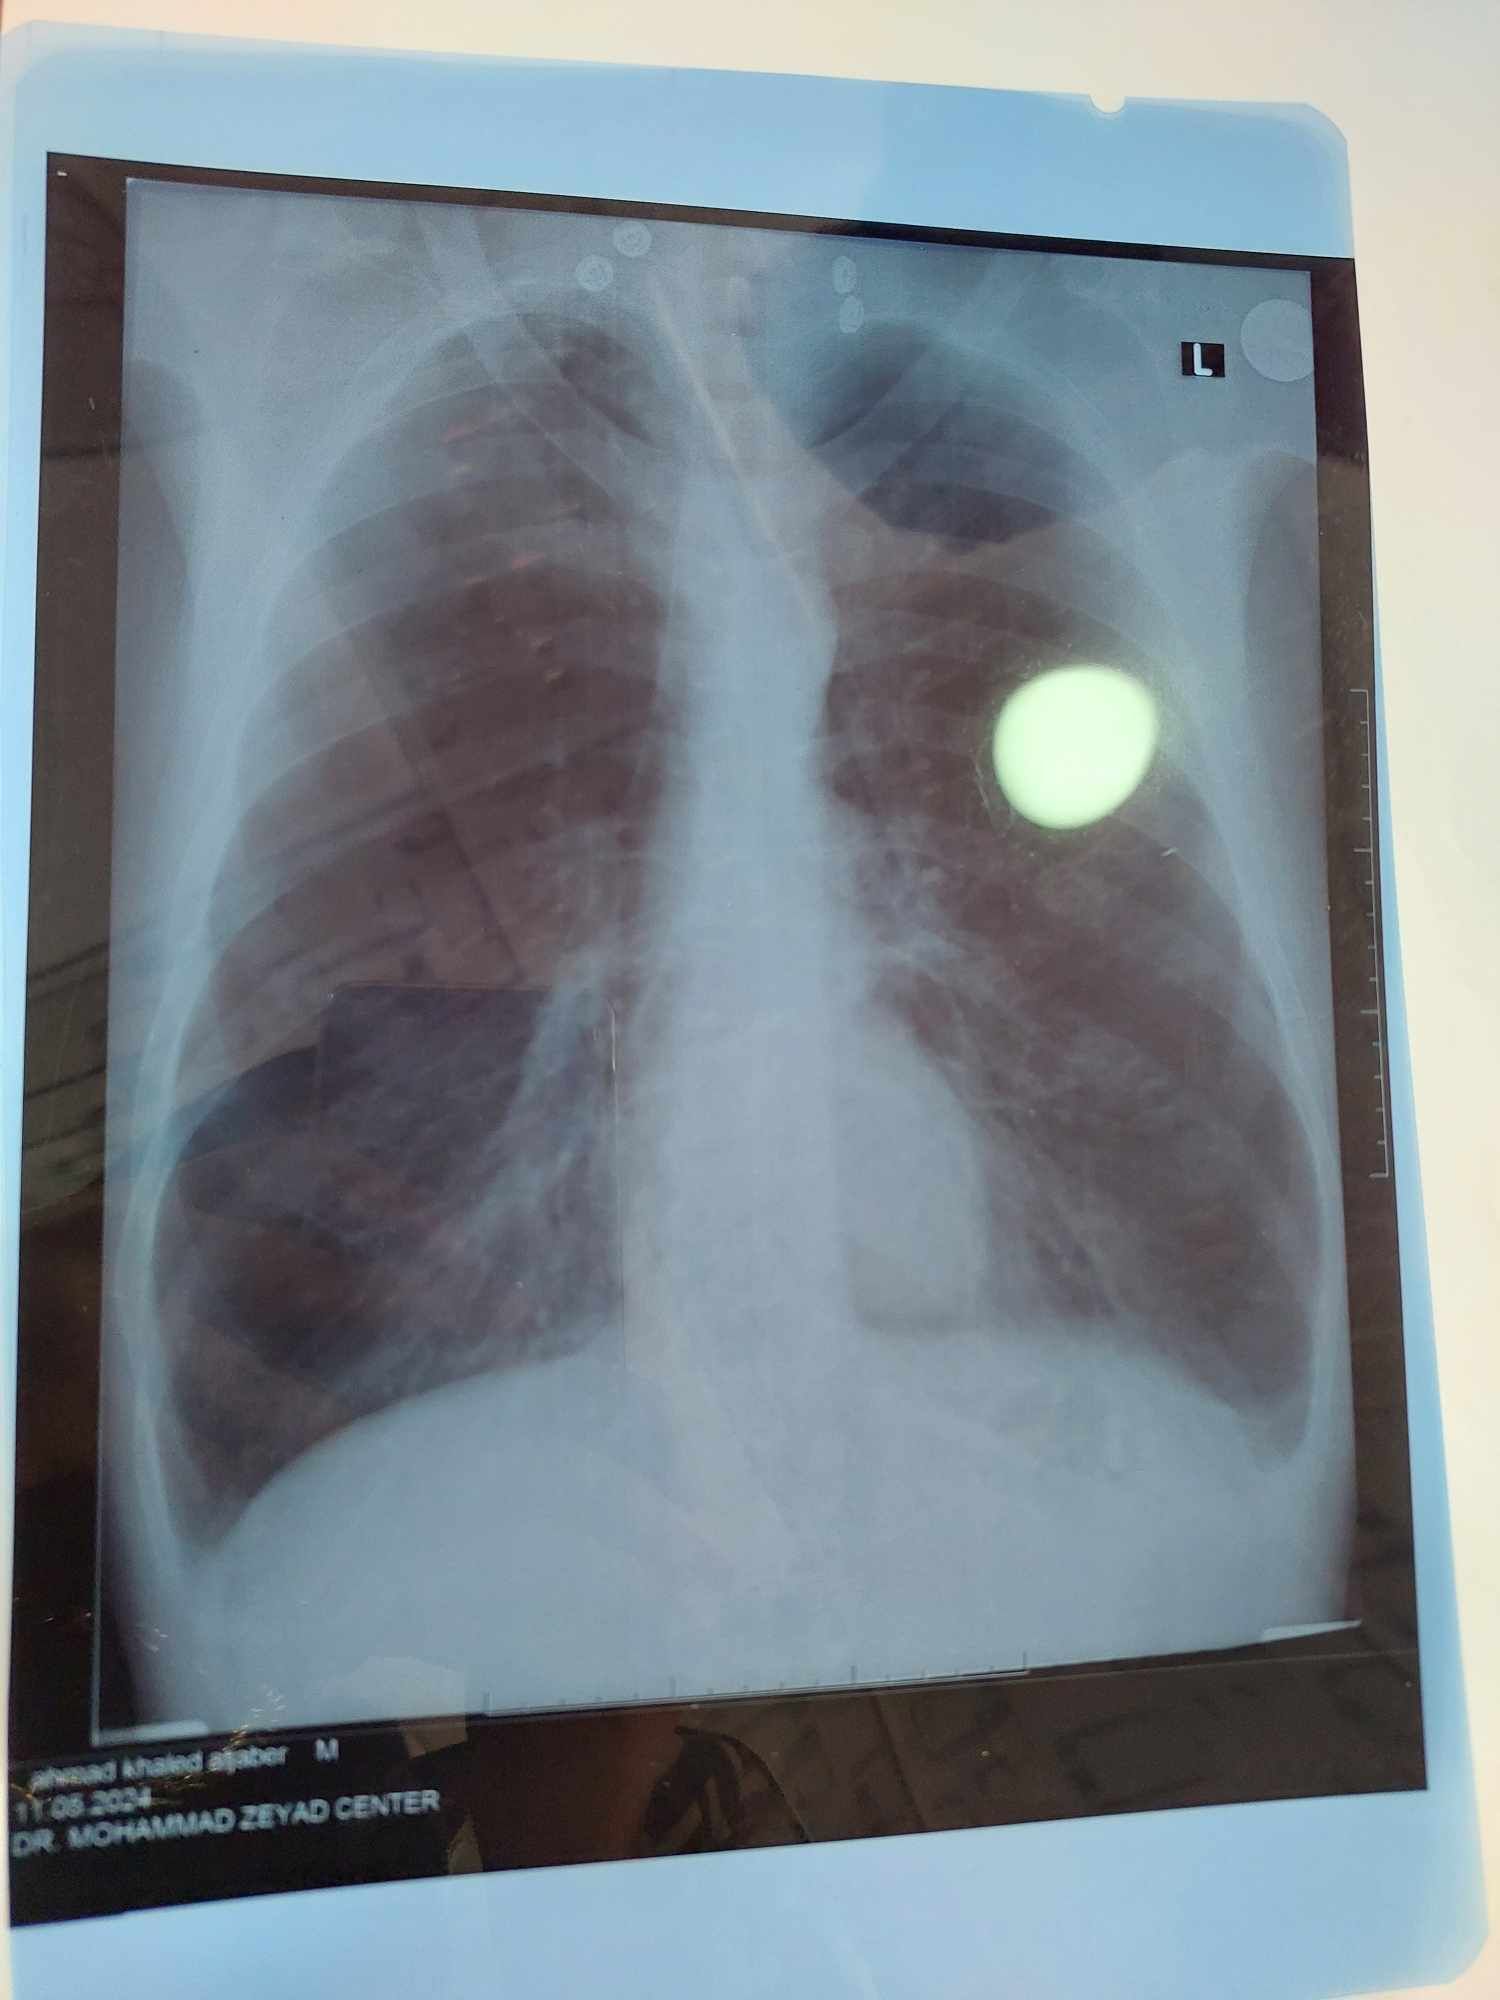

What is the primary diagnosis??

Pulmonary